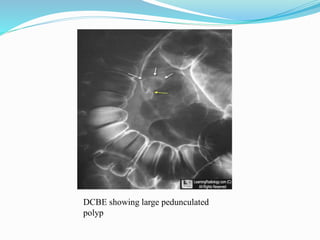

This document discusses colorectal polyps. It defines polyps and describes their types, including neoplastic and non-neoplastic polyps. It discusses adenomatous polyps in depth, noting their malignant potential increases with size over 1cm and villous architecture. Radiological diagnostic methods for polyps including single and double contrast barium enema and CT colonography are explained. The document provides an overview of polyp pathogenesis and genetic syndromes like FAP that increase cancer risk.